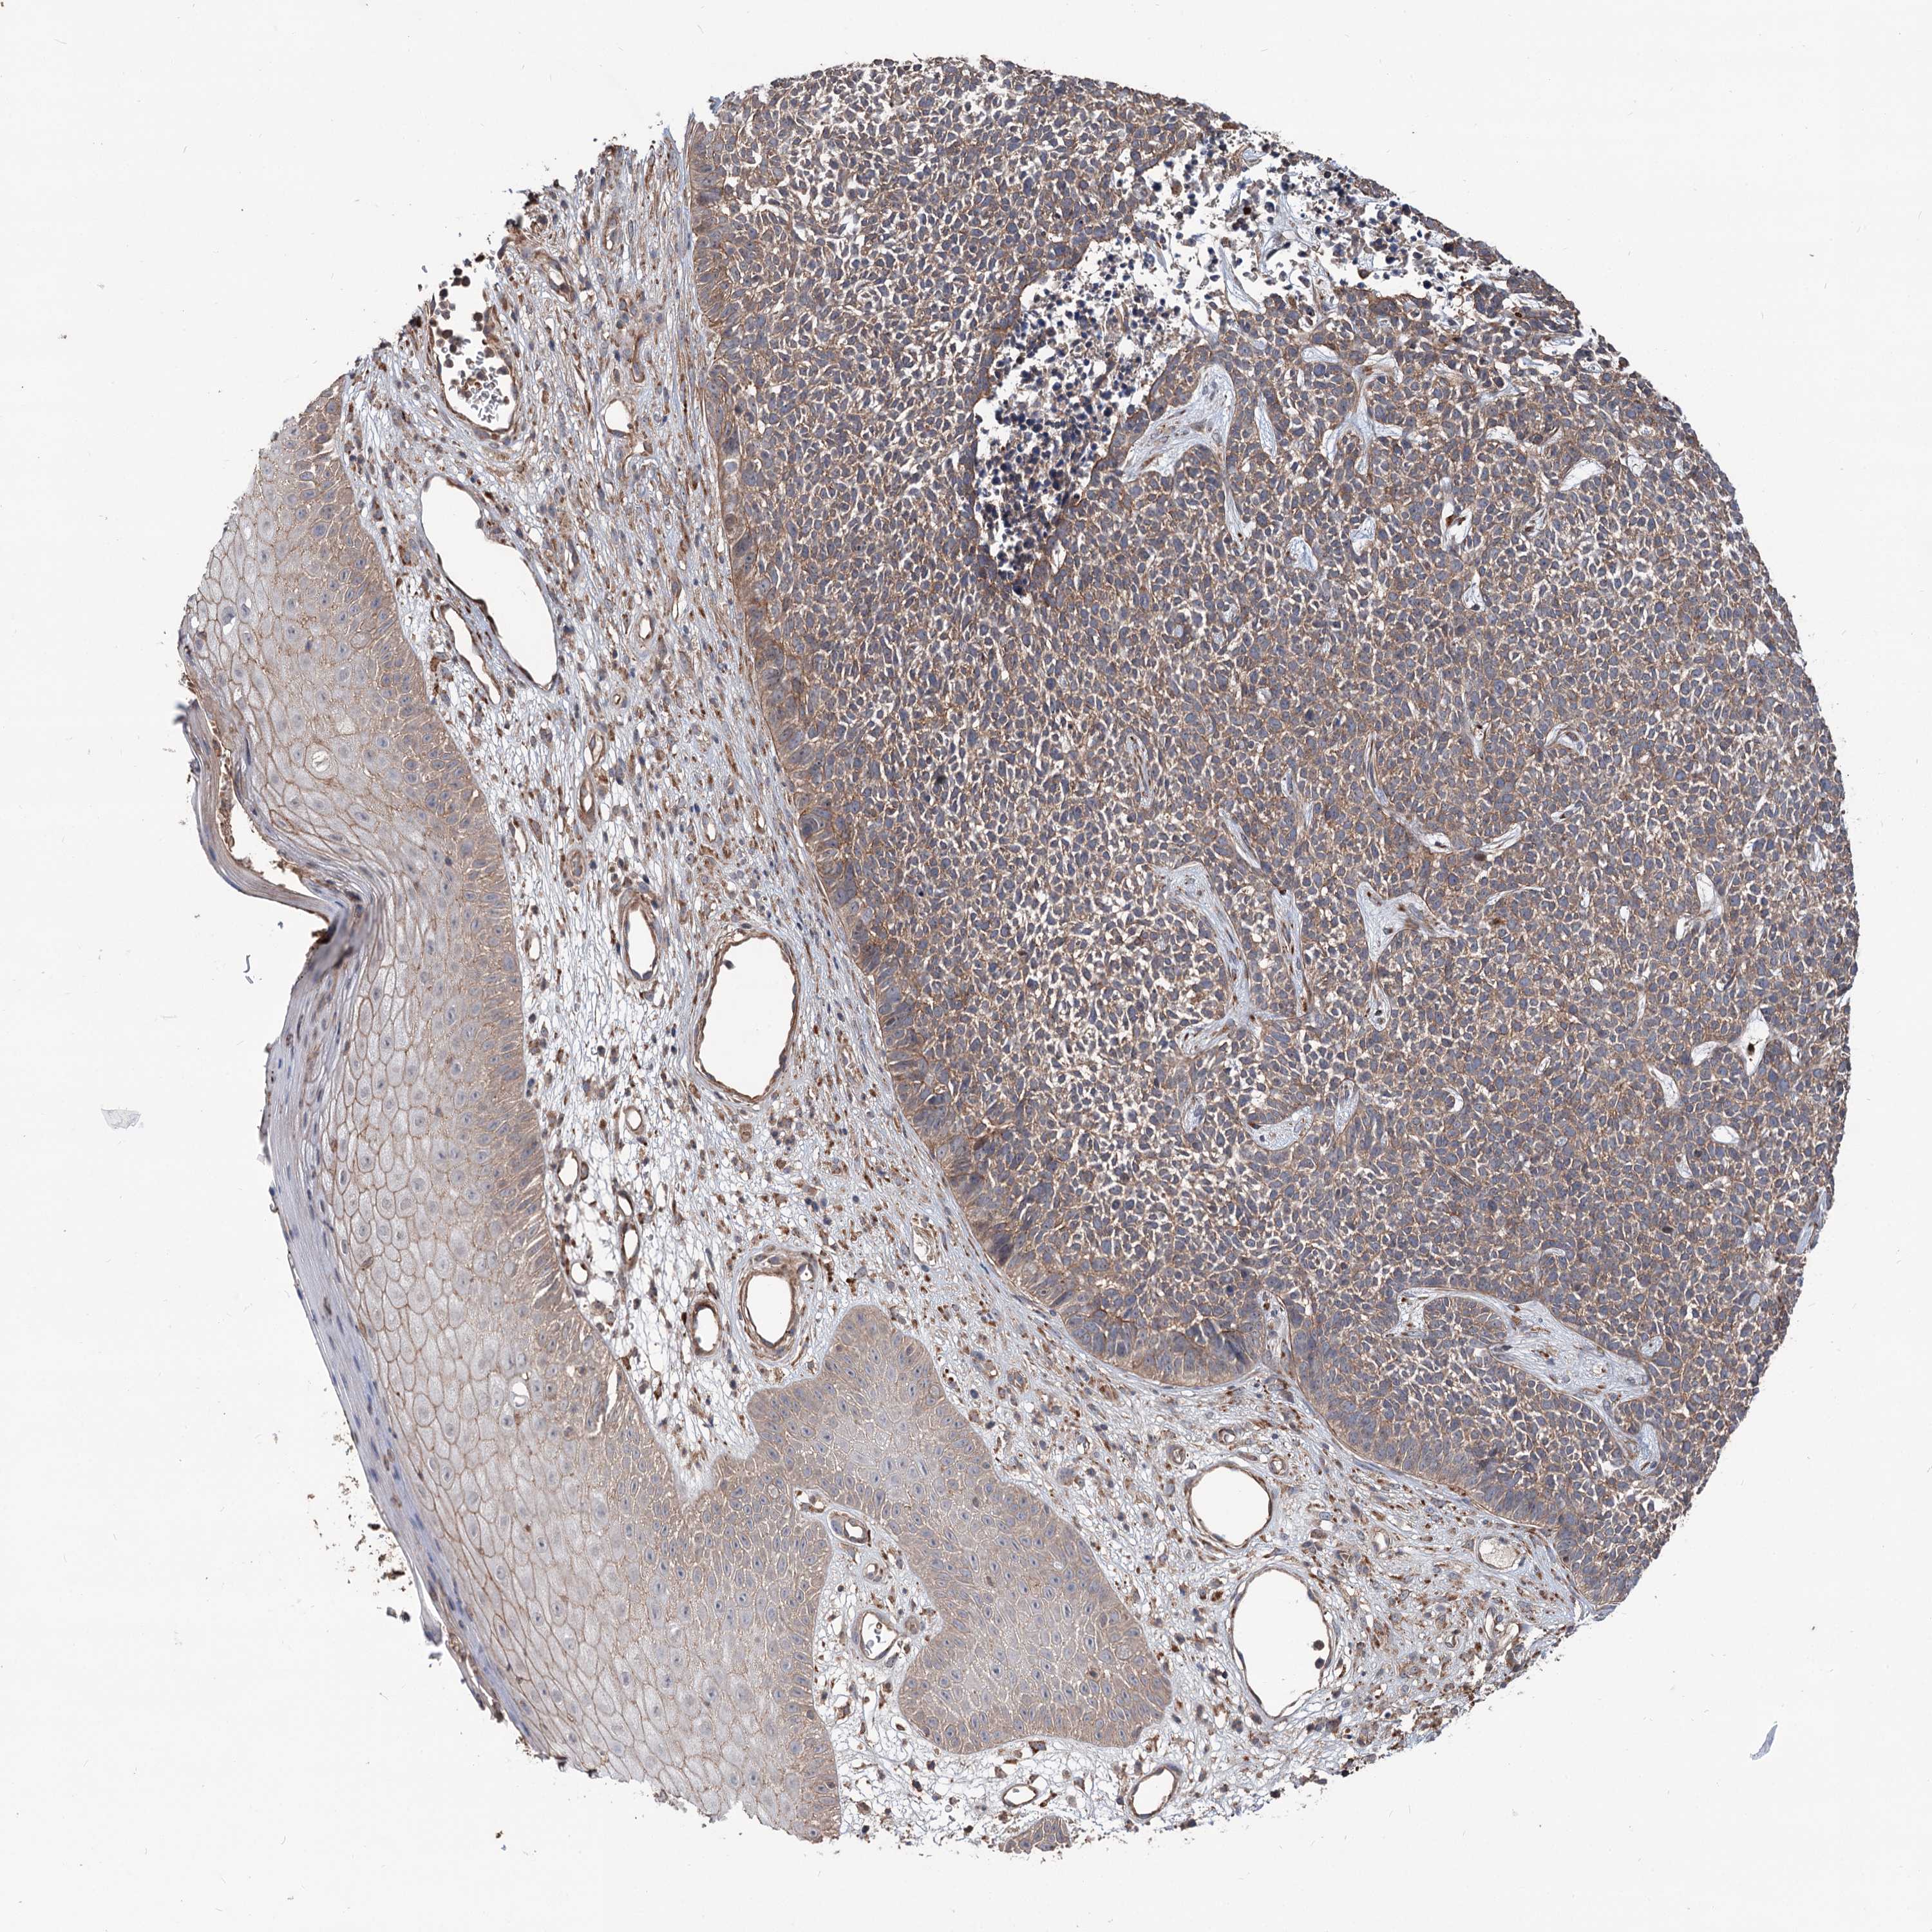

SKIN CANCER - Protein expressioni

A mouse-over function shows sample information and annotation data. Click on an image to view it in a full screen mode. Samples can be filtered based on level of antibody staining by selecting one or several of the following categories: high, medium, low and not detected. The assay and annotation is described here.

Each image is clickable and will lead to virtual microscopy that enables deeper exploration of all samples and also displays staining intensity scores, fraction scores and subcellular localization as well as patient and tissue information for each sample.

Antibody HPA038856

Staining

High

Intensity

Strong

Quantity

>75%

Location

Nuclear

Basal cell carcinoma